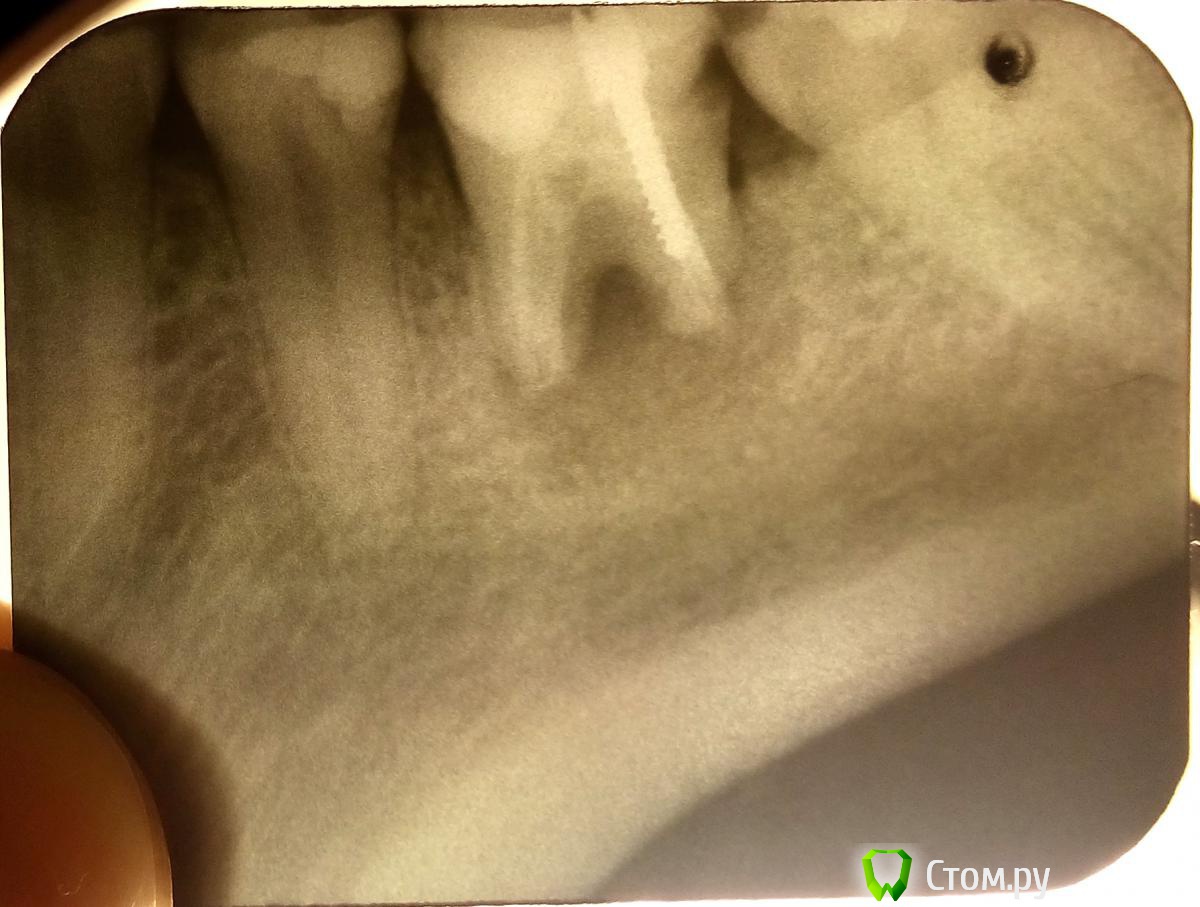

Coffee Опубликовано 20 октября, 2014 Поделиться Опубликовано 20 октября, 2014 Здравствуйте! Стоматолог сказала, что шестой зуб по результатам снимка лечению не подлежит, его нужно удалить, так как он будет являться источником хронической инфекции в организме и последствия могут быть очень разными. Пошла к хирургу на удаление со снимком. Он подтвердил, что зуб лечению не подлежит, но сказал, что раз мне сам зуб не болит, зачем его удалять? Сказал, что могу с ним ходить, пока не заболит. Но у меня с этим зубом такая проблема: десна вокруг него как бы воспалена и легко отодвигается, образуется такой как бы "карман", куда попадает пища и извлечь ее оттуда очень сложно. Сама десна явно не болит, при трогании ее языком есть небольшое болевое ощущение, словно она натерта. Вид у этой картины очень некрасивый. Был небольшой промежуток времени, когда ощущала терпимую боль при нажатии на зуб, потом это прошло. Также был промежуток времени, когда был увеличен лимфоузел на шее с той же стороны, что и этот зуб. После нескольких дней разжевывания прополиса это тоже прошло. Хирург на мои жалобы на десну, сказал, что это поправимо, под обезбаливанием что-то там сделал с этой десной, сказал полоскать раствором соли с йодом и раствором ромашки, чередуя и первые два дня прийти а "перевязку". После этого десна стала "немного красивее", но проблема осталась та же. При чистке зуба зубной нитью - неприятный запах. Думаю, что все же нужно удалить этот зуб. Подскажите, пожалуйста, решение? Ссылка на комментарий

Coffee Опубликовано 20 октября, 2014 Автор Поделиться Опубликовано 20 октября, 2014 вот сейчас только случайно обратила внимание на длину корня этого зуба, она какая-то забавно маленькая)) Вопрос из праздного любопытства, буду благодарна если ответите. Это нормально? (Мне 31 год, если это как-то может быть связано с возрастом) Ссылка на комментарий

sydnik Опубликовано 20 октября, 2014 Поделиться Опубликовано 20 октября, 2014 (изменено) возраст здесь ни при чем,скорее всего патологический процесс уничтожил ваши корни. Изменено 20 октября, 2014 пользователем sydnik 2 Ссылка на комментарий